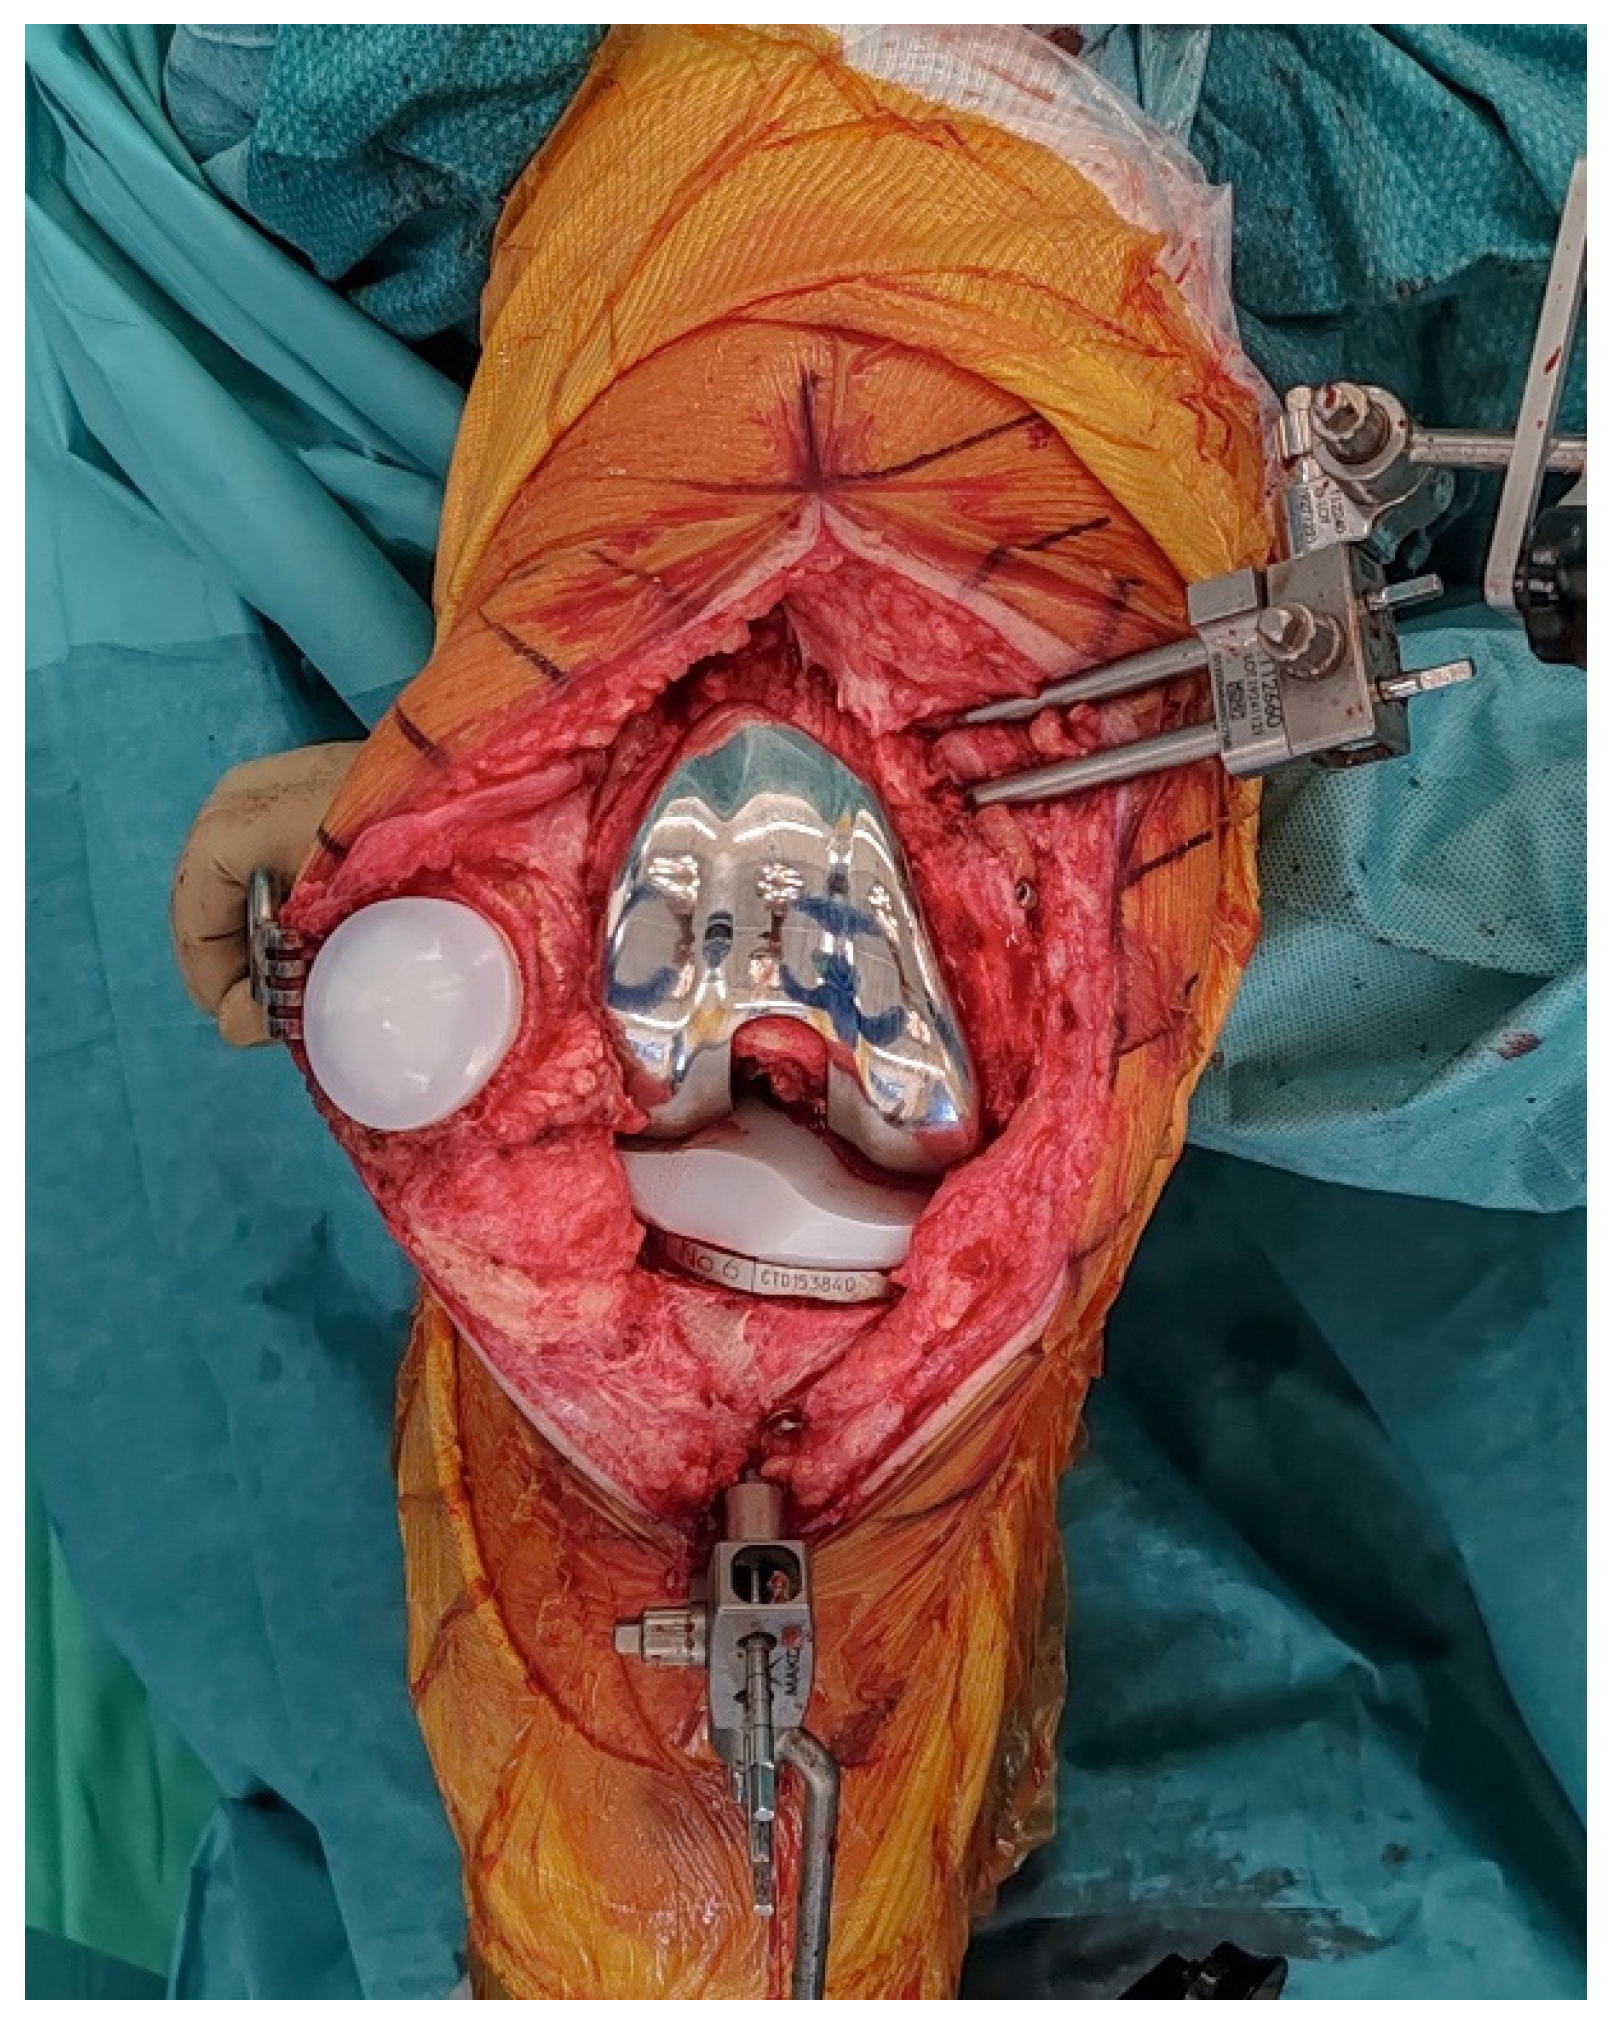

2.8. Final Implantation

Trial components are inserted to confirm flexion–extension gap balance and overall stability (Figure 7). At this stage, balance is assessed both without stress and under standardized varus-valgus stress in terminal extension and at 90° of flexion. Once satisfactory alignment and soft-tissue tension are achieved, definitive cementless condylar-stabilizing components are implanted (Figure 8). We favor CS inserts to obtain coronal stability without ligament releases and without a cam-post mechanism, consistent with bone preservation. Cruciate-retaining implants are used only when the posterior cruciate ligament is clearly competent, and posterior-stabilized (or revision) constructs are selected when anteroposterior stability cannot be ensured with CS inserts or when ligament competence or bone stock are insufficient. Stems, augments, or ligament releases are typically not required. The patella is systematically resurfaced to decrease the risk of future anterior knee pain and revision surgery. Ensure that the final implant position matches the 3D planning and that all the implant press-fit interfaces are fully seated before closure.

Figure 7.

Ligament balancing testing with trial components in place, confirming stable flexion–extension gaps prior to final implantation.

Figure 8.

Final implantation of CS TKA with patellar resurfacing.